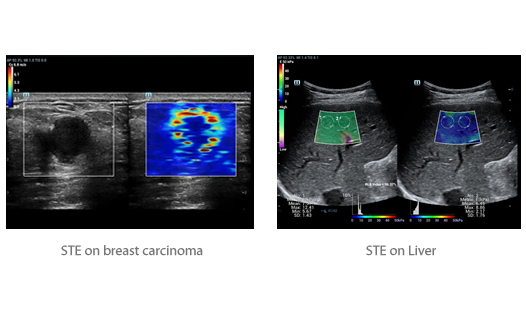

Sejak didirikan, Mindray terus mencari cara baru untuk meningkatkan keandalan diagnostik. Didukung Teknologi ZONE Sonography? terkini, platform ZST+ baru Resona 7 meningkatkan kualitas gambar ultrasound melalui pengambilan zona dan pemrosesan data saluran.

Selain kualitas gambar premium, Resona 7 juga meningkatkan kemampuan penelitian klinis dengan V Flow revolusioner untuk evaluasi hemodinamika vaskular, serta pengambilan penampang tercanggih dari rangkaian data 3D untuk diagnosis CNS pada janin. Kombinasi pengoperasian multisentuh berbasis gerakan yang paling intuitif dengan semua fitur klinis penting membuat Resona 7 menjadi gebrakan baru dalam inovasi ultrasound.